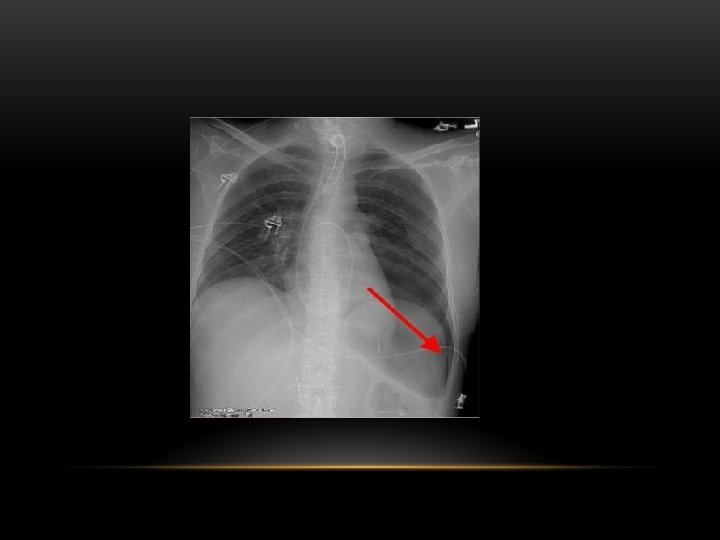

Pneumothorax is air in the pleural space. Radiological criteria: Air (black) in pleural space. No lung markings in pleural space. Recognition of atelectatic lung (lung margin). The lung recoils to a resting state as the negative pressure in the pleura is lost (relaxation atelectasis).

Shift of mediastinum to the opposite side. The mediastinum is held in the middle by balance between pleural pressures. When the negative pressure on the side of the pneumothorax is lost, the mediastinum gets pulled by the normal negative pressure from the opposite side. Progressive shift subsequently could result from a push secondary to tension pneumothorax. Opposite lung gets the entire cardiac output and the vascular markings become prominent.

Causes of pneumothorax: -Burst small blebs o bullae. -Empyema -Trauma -Certain forms of interstitial pulmonary disease -Pneumocytosis carinii pneumonia -Metastasis (rarely)